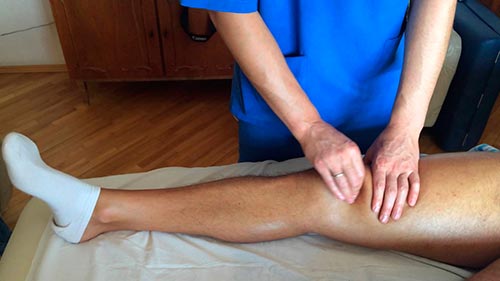

Мануальная терапия и массаж

Остеоартроз коленных суставов успешно лечится массажем. Он способствует укреплению мышц, снятию тонуса, улучшению кровообращения и т.д. Можно проходить сеансы массажа в больнице или проводить его самостоятельно, следуя рекомендациям врача.

Устойчивый результат появится после 20 сеансов. Закрепить результат поможет его повторение (2-3 раза в год).

Непосредственно перед процедурой колени и окружающие их ткани нужно разогреть. Дальше следует двигаться снизу вверх, именно такое направление имеют лимфатические сосуды. Строго запрещено массажировать область под коленом, поскольку есть вероятность повреждения расположенных там нервных стволов. Если есть возможность, лучше сделать массаж всей ноги, начиная от ступни и заканчивая бедром.

При гонартрозе колена лечение проводится с помощью мануальной терапии. Она проводится исключительно по назначению врача. Позволяет вернуть суставу подвижность и убрать болевые ощущения. Плюс ко всему этот метод лечения усиливает эффект от применения лекарственных средств.

Сеансы мануальной терапии рекомендуется проводить не менее 3 раз в год.